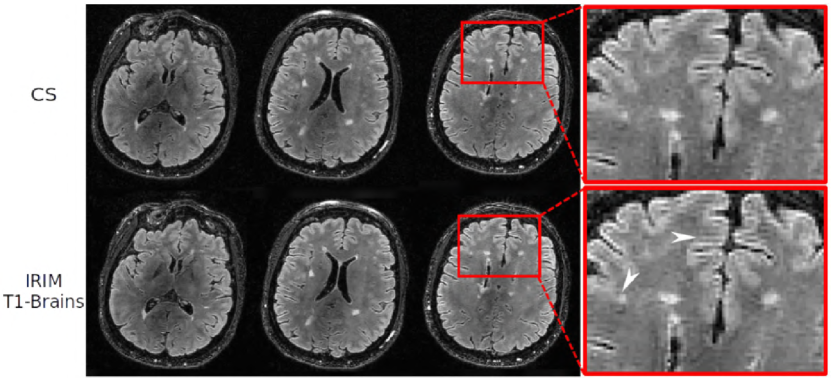

Fig. 6 depicts the results of the lesion simulation experiment. The graphs in Fig. 6(a) show the reconstructed intensity in the centre of the lesion as a function of the simulated intensity. Furthermore, different acceleration factors were applied, whereas applying the IRIM trained on the different modalities individually and all of them simultaneously, as well as the conventional CS reconstruction algorithm. Observe that the intensities are expressed through the multiplication factor of the Gaussian profile added to the original signal. Also, noise was added to the data, so that reference intensity fluctuates somewhat, as indicated by the black line. For 4-fold acceleration, all models had comparable performance, i.e. within a margin of 5%, and showed no bias. For higher accelerations the IRIM trained on the -weighted knee dataset resulted in the highest intensities, even overestimating the reconstructed lesion intensity by 10%, whereas CS underestimated it by 40%. IRIMs trained on the -weighted brain dataset and all datasets underestimated the intensity by 15% and the IRIM trained on the -weighted brain dataset by 45%. This also can be observed in the reconstructions in Fig. 6(b) of the simulated lesion intensity equal to 1.0. The IRIM trained on the -weighted brain dataset and ALL datasets show slightly enhanced the signal compared to CS. The IRIM trained on the -weighted brain data yields degraded quality whereas the IRIM trained on the -weighted knee dataset is able to reconstruct a brighter lesion with enhanced contrast, but also resulting in a smoother image.

Finally, Fig. 7 shows FLAIR images of an MS patient, reconstructed with the CS and the most efficient model, the IRIM trained on the -weighted brain dataset. Visually, white matter lesions seen in the CS images (here taken as the reference) can also be identified in the IRIM reconstructions. Confirming the simulation experiment, the IRIM slightly enhanced the signal compared to CS. This is visible both in the lesion as well as in the minute cortical gyrus texture amplification (see arrows).